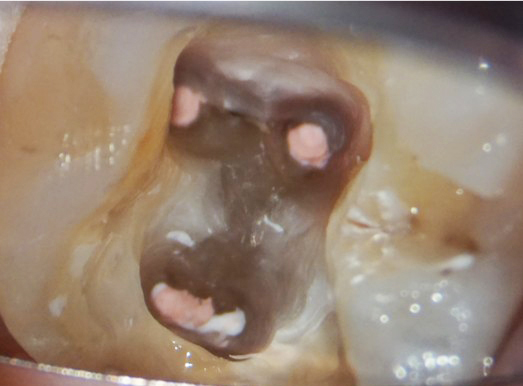

POINTマイクロスコープを用いた精密治療

根管の中は肉眼で見ることができず、従来の治療はレントゲンを参考にしながら、手の感覚を頼りに探り、治療をしていた側面があります。そうすると見落としがおき、感染源が残ってしまい再治療が必要になるケースも出てきます。

マイクロスコープで拡大し、根管内を詳細に観察することで感染源を細部まで取り除き、再発を断ちます。

当院の症例紹介

精密根管治療の症例

Before

After

| 通院目的 | 右下6番部の根尖病変の治療 |

| 処置内容 | 感染根管治療 |

| 備考 | 他院で根管治療を受けていたが、経過不良のため、マイクロスコープを用いた根管治療を行っている当院に、患者が当院での治療を希望し来院された。 |